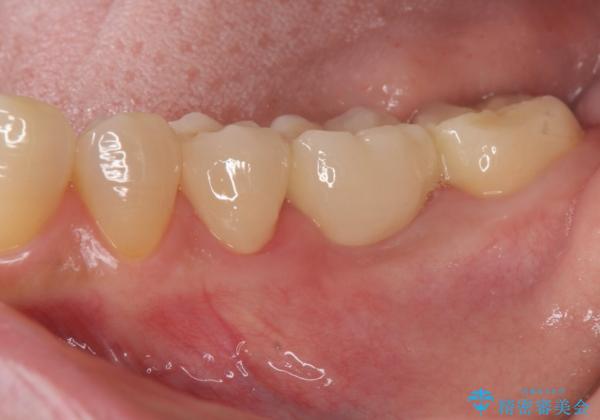

- 他院で行われた抜歯後の機能回復について相談に来院されました。

インプラント治療、入れ歯と比較し、前後の銀歯や詰め物の問題も一緒に治療のできるブリッジ治療を選択されました。

ブリッジは早期に審美性・機能性を回復できる治療法です。